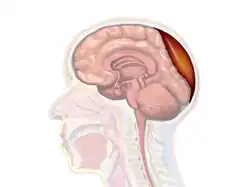

Epidural hematoma is when bleeding occurs between the tough outer membrane covering the brain (dura mater) and the skull.[4] When this condition occurs in the spinal canal, it is known as a spinal epidural hematoma.[4]

Pathophysiology

The break of the temporal bone causes bleeding from the middle meningeal artery,[4] hence epidural bleeding is often rapid as arteries are high-pressure flow. In 10% of cases, however, it comes from veins and can progress more slowly.[10] A venous hematoma may be acute (occurring within a day of the injury and appearing as a swirling mass of blood without a clot), subacute (occurring in 2–4 days and appearing solid), or chronic (occurring in 7–20 days and appearing mixed or lucent).[3]

In adults, the temporal region accounts for 75% of cases. In children, however, they occur with similar frequency in the occipital, frontal, and posterior fossa regions.[3] Epidural bleeds from arteries can grow until they reach their peak size 6–8 hours post-injury, spilling 25–75 cubic centimeters of blood into the intracranial space.[8] As the hematoma expands, it strips the dura from the inside of the skull, causing an intense headache. It also increases intracranial pressure, causing the brain to shift, lose blood supply, be crushed against the skull, or herniate. Larger hematomas cause more damage. Epidural bleeds can quickly compress the brainstem, causing unconsciousness, abnormal posturing, and abnormal pupil responses to light.[14]